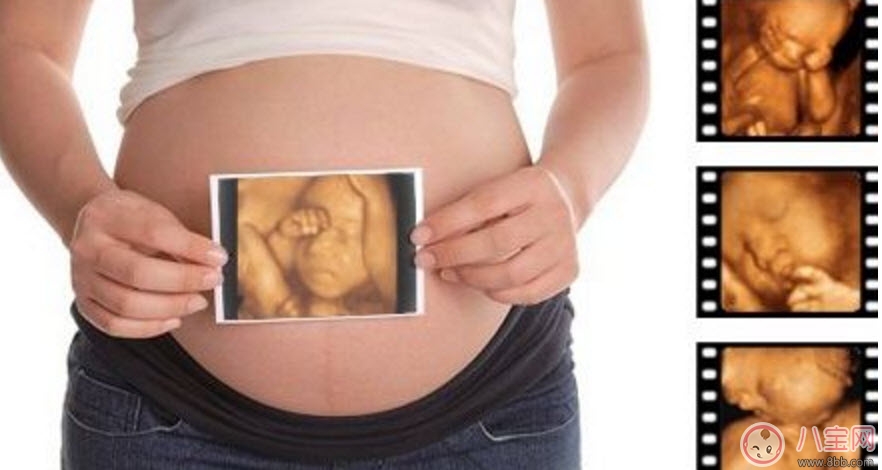

孕婦的羊水適量的話就可以做這項(xiàng)檢查。但是受胎兒體位、胎盤以及孕期不同等方面的因素影響,專家建議最佳做四維彩超的時(shí)間應(yīng)該是12-30周,這個(gè)時(shí)期就可以完全獲取到胎兒的面部以及身體等結(jié)構(gòu)的圖像。懷孕十個(gè)月的時(shí)候里最少要做3次的四維彩超,時(shí)常觀察胎兒成長。

1、一般整個(gè)孕期做三次四維彩超,懷孕的22~26周做四維彩超最佳,但是具體時(shí)間也是因人而異的。

2、孕婦在22-26周的階段,做四維彩超不需要憋尿,也不需要空腹。孕婦指需要在規(guī)定的時(shí)間內(nèi)到醫(yī)院進(jìn)行檢查即可。

3、在四維彩超檢查前,孕婦最好將自己的上衣和褲子分開穿。而在四維彩超的檢查中,醫(yī)生主要是通過檢查的儀器,對胎兒當(dāng)前的面部發(fā)育,還有心臟,大腦,脊椎等有沒有存在發(fā)育缺陷的情況進(jìn)行一個(gè)檢查。

4、做四維彩超時(shí),孕媽媽一定要保持良好的心態(tài),整個(gè)做檢查過程大概會持續(xù)20分鐘左右。